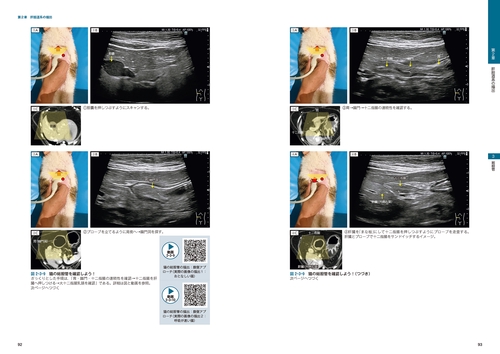

犬と猫の腹部超音波の基本知識を学べるレッスン書。購入後、断截済み!直ぐにスキャン出来ます!超音波検査の基本知識/肝胆道系/脾臓/腎臓・尿管- タイトル: 犬と猫の腹部超音波の描出レッスン 上巻- 著者: 戸島雅史- ISBN: 978-4-86368-217-7- 出版社: 緑書房- 価格: 定価 13,200円 (税別 12,000円)- ページ数: 122クリップ・360枚- 内容: 超音波技術の基本知識/腹部超音波/解剖/実習/画像ご覧いただきありがとうございます。